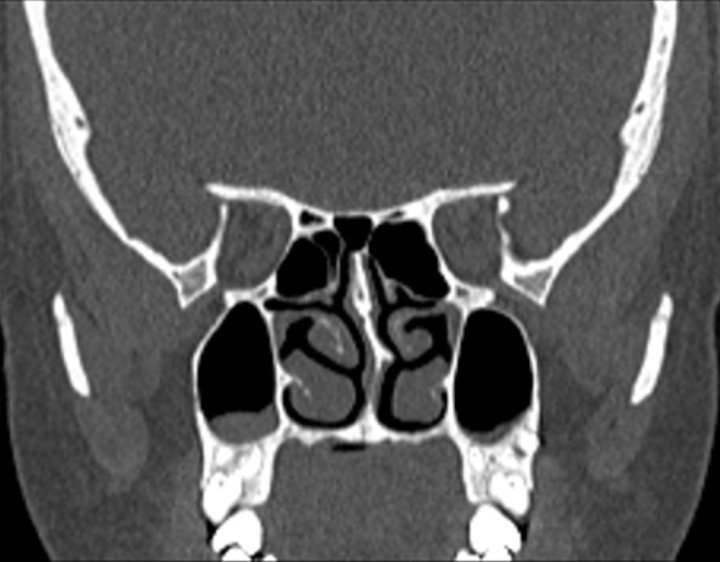

004